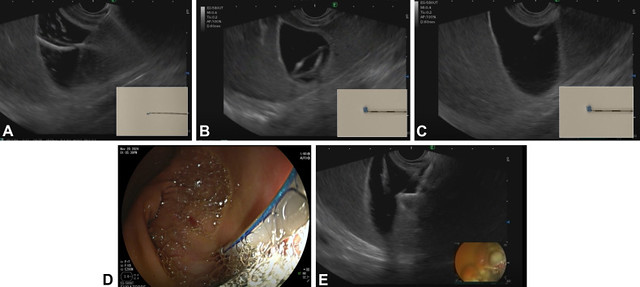

Overview of suture-assisted cholecystogastrostomy with (A) advancement of the suture needle into the gallbladder followed by deployment of the suture tags, (B) gentle tension applied to the suture results in formation of a securement loop, (C) withdrawal of the needle and additional tension on the suture, which allows for manipulation of the gallbladder, (D) suture anchor and lock deployed through the echoendoscope under endoscopic visualization, and (E) freehand deployment of a lumen-apposing metal stent.